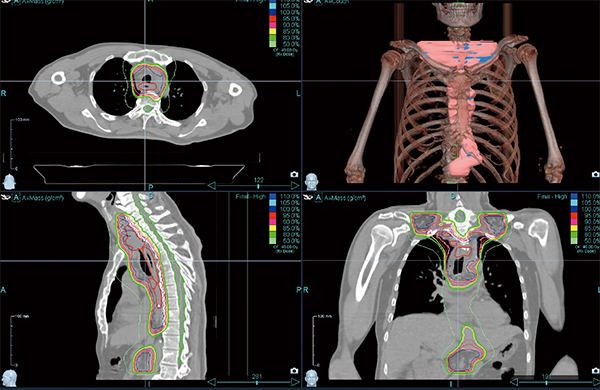

Radixactは,IMRTはもとより40cm以上にわたる長い病巣に対しても,つなぎ目のない放射線治療が可能である。このことによって,頸部や腹部リンパ節まで進展した食道がん(図1)や,上頸部まで転移のある肺がん,通常の放射線治療では根治照射が難しい両側頸部リンパ節転移のある進行がんに対しても,根治治療が比較的容易に計画できるようになった。病巣の進展によっては根治治療を断念せざるを得ない症例にも根治的放射線治療が可能になったことは,長く放射線治療にかかわってきた身としては非常にありがたく,うれしいことである。

図1 両側頸部および腹部リンパ節転移のある進行食道がん症例

両側頸部リンパ節転移があると,従来の放射線治療(3D-CRT)では多くの症例で根治的放射線治療は困難となるが,IMRTにより根治的治療が可能となる。Radixactを利用することにより,腹部リンパ節転移に対してもつなぎ目のない放射線治療が可能となった。